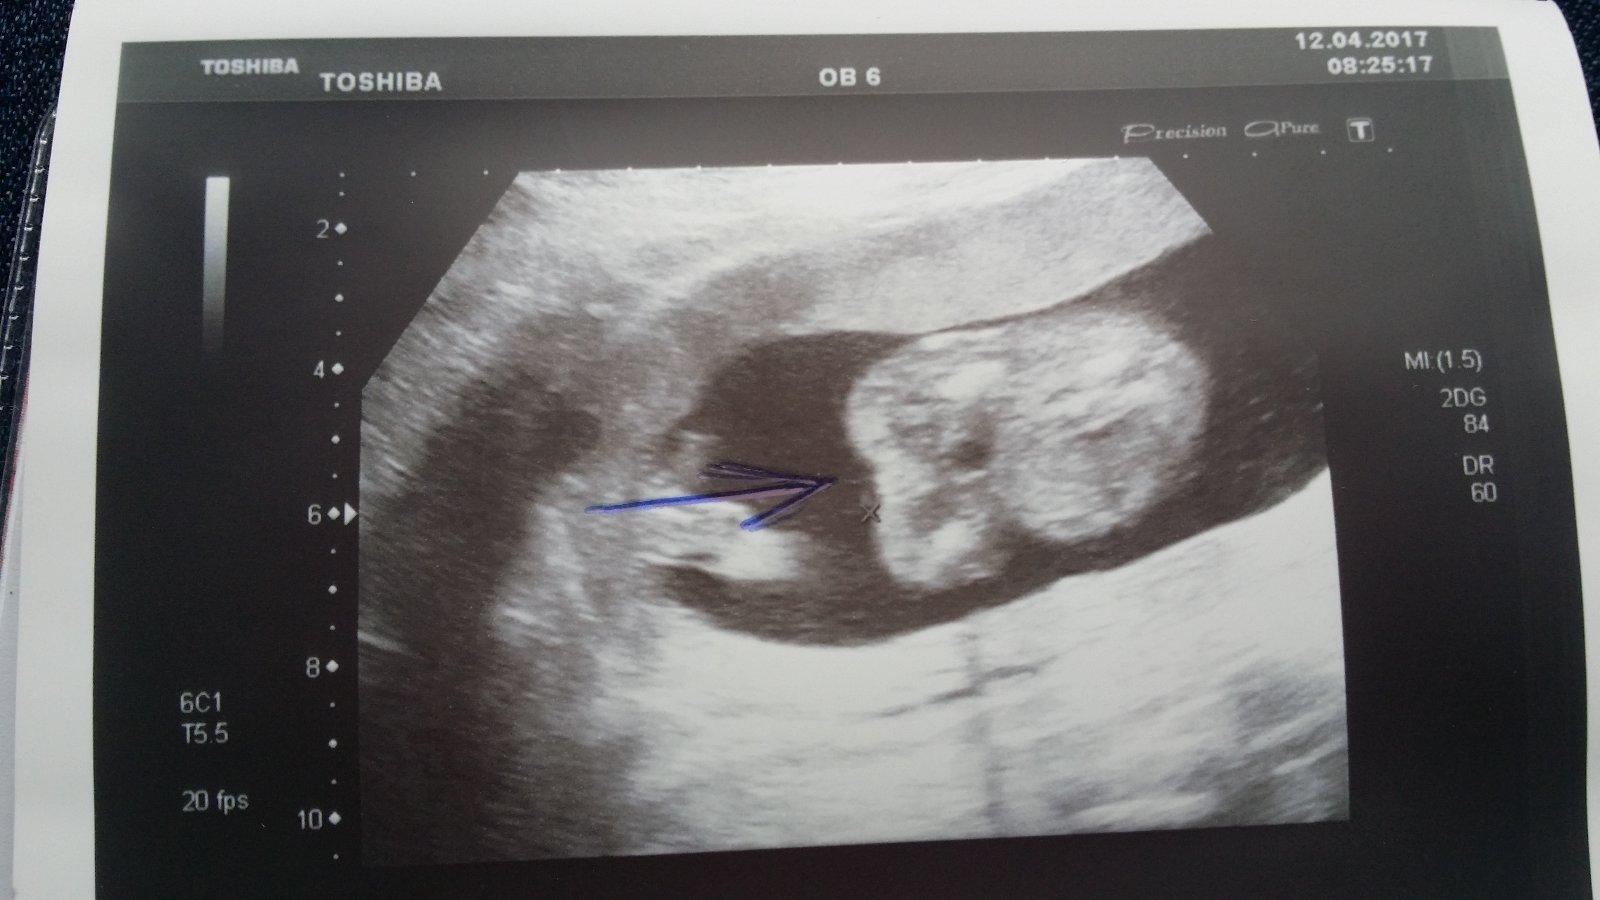

Ahoj maminky a budoucí maminky 😉 Prosím, poradila byste mi některá, co vidíte na fotce z ultrazvuku ve 20. týdnu za pohlaví? Určitě jste foteček viděly už mraky, proto vás žádám o radu...Nechci nikoho ovlivnit, proto svůj tip řeknu později 🙂 Děkuju moc!!!

Ahoj, bohužel jediné co vidím, je sladké malé miminko, ale pohlaví z této fotky určit nelze. Taky je dost brzy, ale já jsem kolem toho 14 tt pindíka zahlídla 🙂 Tohle zatím vypadá na holčičku, ale to je opravdu jen tím, že není nic jako pinďa přímo vidět!

@sophien mám tu stejnou fotku, moje je holčička. Ale na tvé fotce vidím nějaký canfrňour...😕 tak nevím no...

@novamamina No právě, ta tvoje tam nic nemá,tak já fakt nevím😀

@sophien Právě no. Já bych se u tebe teda přikláněla spíš ke klučinovi 🙂. Dr ti řekla holku?

@novamamina Právě holku, no, prý podle pohlavních valů🙂